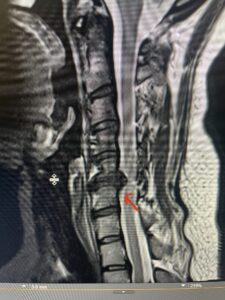

This 47-year-old male who four months prior was lifting weights developed sharp pain in his neck. After that he developed progressive numbness in his arms, neck pain and headache. He said that the right arm was worse than the left. On examination the patient had long tract weakness on the right side which included his triceps, finger extensors, hip flexors, and dorsiflexors. The patient did not have hyperreflexia. MRI (Fig. 2) demonstrated a massive, extruded disc herniation with severe cord compression. The patient because of progressive myelopathy and spinal cord compression was indicated for anterior cervical discectomy and fusion at C4-5 (Fig. 3). Patient had significant improvement of weakness and numbness post operatively.

Fig. 2a Sagittal T2-weighted cervical MRI demonstrating large C4-5 herniated disc with spinal cord compression (red arrow)

Fig 2a Sagittal and axial T2 weighted cervical MRIs demonstrating large C4 5 herniated disc with spinal cord compression red arrows